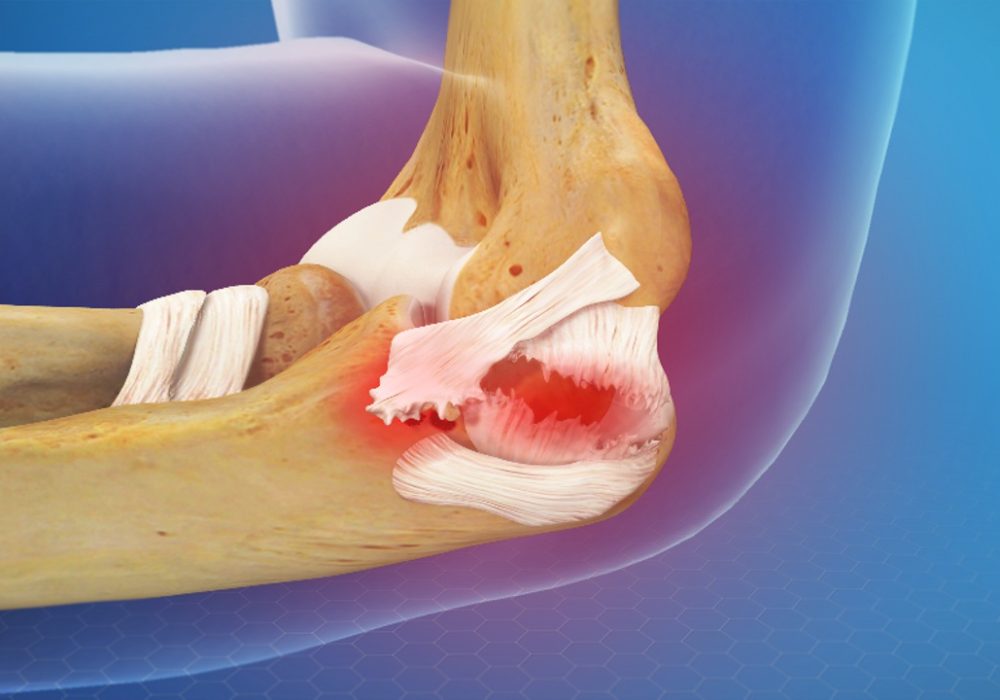

The elbow is a complex joint stabilized by multiple ligaments that provide strength and allow a wide range of motion. Injuries involving multiple ligaments of the elbow can lead to joint instability, pain, and functional impairment. Elbow multi ligament reconstruction is a specialized surgical procedure aimed at restoring stability and function in patients with severe ligament injuries. This article provides an overview of the causes, diagnosis, surgical techniques, and recovery associated with elbow multi ligament reconstruction.

The elbow joint is stabilized primarily by three ligament complexes:

- Medial Collateral Ligament (MCL): Provides valgus stability (prevents the elbow from bending outward).

- Lateral Collateral Ligament (LCL) Complex: Provides varus stability (prevents the elbow from bending inward) and posterolateral rotatory stability.

- Annular Ligament: Encircles the radial head and stabilizes the proximal radioulnar joint.

Injuries to one or more of these ligaments can cause elbow instability, leading to pain, weakness, and limited motion.